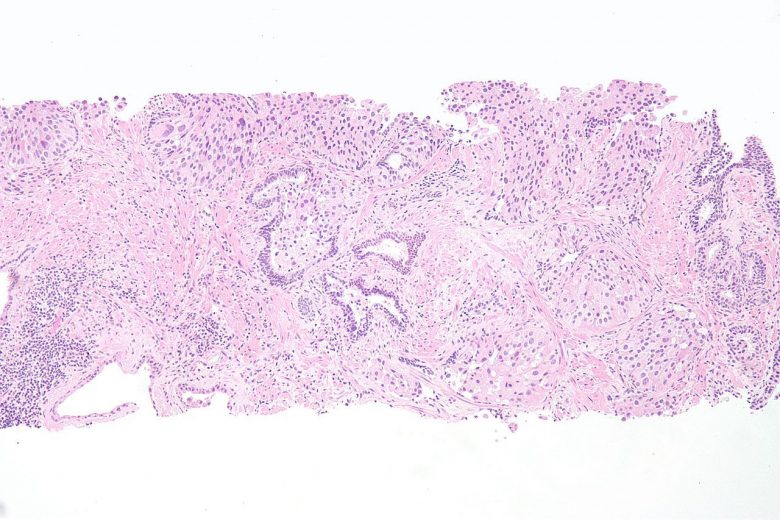

Pancreatic cancer

“Pancreatic cancer can develop from two kinds of cells in the pancreas: exocrine cells and neuroendocrine cells, such as islet cells. The exocrine type is more common and is usually found at an advanced stage. Pancreatic neuroendocrine tumors (islet cell tumors) are less common but have a better prognosis.”

Image Credit: Nephron / Wikimedia Commons.